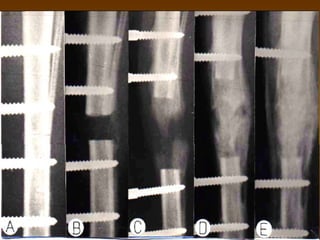

INTERLOCKING NAILINTERLOCKING NAIL

 Controls torsion and axial loadsControls torsion and axial loads

 AdvantagesAdvantages

 Axial and rotational stabilityAxial and rotational stability

 Angular stabilityAngular stability

 DisadvantagesDisadvantages

 Time and radiation exposureTime and radiation exposure

 Stress riser in nailStress riser in nail

 Location of screwsLocation of screws

 Screws closer to the end of the nail expand the zoneScrews closer to the end of the nail expand the zone

of fxs that can be fixed at the expense of constructof fxs that can be fixed at the expense of construct

stabilitystability

Intramedullary NailsIntramedullary Nails

 ““Internal Splint”, Load SharingInternal Splint”, Load Sharing

 Nail itself should resist bending andNail itself should resist bending and

torsiontorsion

 The bone should resist axial loadingThe bone should resist axial loading

 Strength => wall thickness, diameter, andStrength => wall thickness, diameter, and

materialmaterial

 stiffness => 4th power of the diameterstiffness => 4th power of the diameter

 Type of fracture –transverse, oblique, orType of fracture –transverse, oblique, or

complex determines some stabilitycomplex determines some stability

 Working lengthWorking length is area that spansis area that spans

fracture between points of fixation.fracture between points of fixation.

 In bending,In bending, stiffnessstiffness inverselyinversely

proportional to square of lengthproportional to square of length

 Torsional rigidityTorsional rigidity is inverselyis inversely

proportional to lengthproportional to length

 Gripping strength is resistance to slippingGripping strength is resistance to slipping

at bone-implant interface. Increased byat bone-implant interface. Increased by

increasing cortical contact.increasing cortical contact.

 Nail can twist or slip with torsional loadingNail can twist or slip with torsional loading

which allows angulationwhich allows angulation

interlockinginterlocking

 Dynamic fixationDynamic fixation controls bending andcontrols bending and

rotation, but allows axial loadingrotation, but allows axial loading

 Static lockingStatic locking controls bending, rotation,controls bending, rotation,

and axial loadingand axial loading